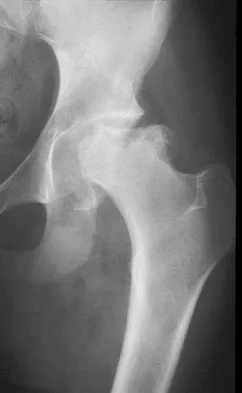

Figure 2 shows the radiograph of a 72-year-old woman who reports pain after a fall. History includes several years of increasing thigh pain and limb shortening. Management consisting of an extensive work-up for infection reveals normal laboratory studies, a positive bone scan, and a negative hip aspiration. What is the most likely etiology of this complication?

Explanation

The patient has a midstem periprosthetic fracture, which commonly results in loosening of the prosthesis. Patients who have a large amount of bone loss may require an allograft with the surgical reconstruction. Although the patient reported a fall, her history is also consistent with preexisting loosening of the prosthesis. Chronic infection has been shown in up to 16% of these fractures; however, the patient's work-up revealed no infection. Garbuz DS, Masri BA, Duncan CP: Periprosthetic fractures of the femur: Principles of prevention and management, in Cannon WD Jr (ed): Instructional Course Lectures 47. Rosemont, IL, American Academy of Orthopaedic Surgeons, 1998, pp 237-242. Bethea JS III, DeAndrade JR, Fleming LL, Lindenbaum SD, Welch RB: Proximal femoral fractures following total hip arthroplasty. Clin Orthop 1982;170:95-106.